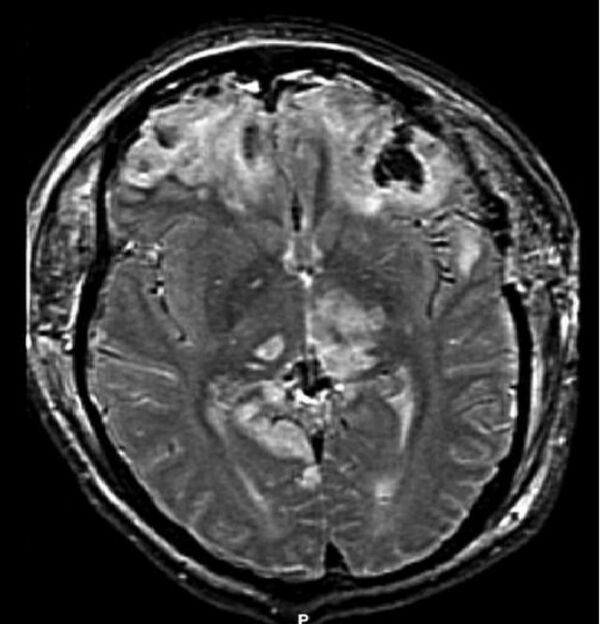

Ушиб головного мозга (лат. contusio cerebri) — черепно-мозговая травма, при которой происходит поражение непосредственно тканей головного мозга, всегда сопровождается наличием очага некроза нервной ткани. Наиболее часто очаги повреждения располагаются в области лобных, височных и затылочных долей. Повреждения, развившиеся при травме, могут быть как односторонние, так и двухсторонние[2].

Ушиб мозга тяжелой степени характеризуется длительной потерей сознания после травмы (от нескольких часов до нескольких недель). Обычно выражено двигательное возбуждение. Наблюдается доминирование стволовых неврологических симптомов (множественный нистагм, нарушения глотания, двухсторонний мидриаз или миоз, горметония и др.). Могут выявляться парезы конечностей. Часто выражены менингеальные симптомы. Возможны переломы костей свода черепа и массивное субарахноидальное кровоизлияние. Тяжёлые ушибы мозга часто приводят к летальному исходу[2][4].